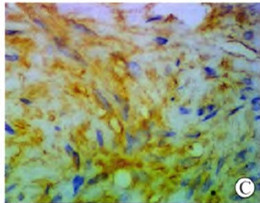

病理巨检:结节一个,大小为3cm×2.5cm×2.5cm,无包膜,肿瘤境界清楚,切面灰白色,均质实性,质地柔韧,无出血及坏死。镜下观察:肿瘤由分化好的梭形细胞组成,边界清楚,胞质丰富,深粉红色;核呈杆状,两端钝圆,染色质细腻,无异型,无核分裂象,无坏死,瘤细胞聚集成束,呈编织状排列(图2A)。免疫组化:desmin+(图2B、2C),SMA+,Vimen.tin+,NSE-,Bcl-2-,CDll7-,S-100-,CD34-。

图2B 瘤细胞desmin胞浆阳性(SP×200)

图2C 瘤细胞desmin胞浆阳性(SP×400)